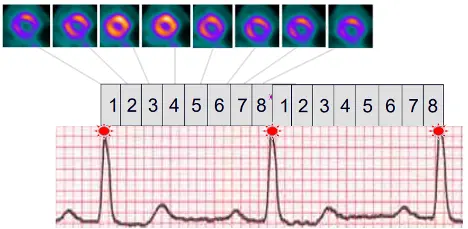

tl;dr: We collect transmission and perfusion images and superimpose them on one another. The CT and perfusion contours of the heart should be properly aligned (co-registration).

- Scout image to localize the heart

- Transmission scans – most commonly done with low-dose CT AC

- Emission scans

- Patient is

-1753742157382.webp)

CT Acquisition

- Gated (ECG)

- Often you’ll see 8 or 16 bins between R-R intervals. We can go to the end-diastolic frame and calculate EDV and the end-systolic frame (e.g. frame 4 in example below) and calculate ESV → use ESV and EDV to calculate EF for these patients.

-1753742216064.webp)